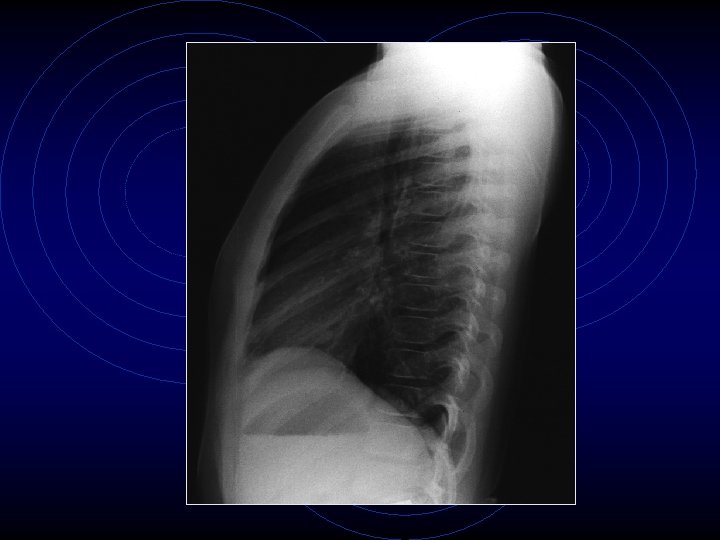

• Le indagini ematochimiche evidenziavano una modesta leucocitosi neutrofila (GB: 13340, N: 89, 3%) con PCR nei limiti della norma (< 0, 46 mg/dl) così come transaminasi, ionogramma, glicemia, azotemia, creatininemia, elettroforesi delle proteine • Veniva quindi eseguita radiografia del torace che dimostrava una modesta iperespansione dei campi polmonari bilateralmente con accentuazione del disegno polmonare